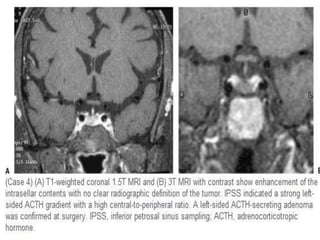

Coronal T1 and T2-weighted images and T1-weighted images before and after gadolinium. In

this patient the lesion in the pituitary gland is only detectable after the administration of

intravenous contrast. The differential diagnosis: pituitary microadenoma or Rathke's cleft cyst.

Cystic rounded lesion within the gland which appears of low signal at the T1WI and of bright

signal at the T2WI. No contrast uptake within the lesion at the enhanced study, related to cystic

microadenoma. The stalk is deviated to the right side.

A case of pituitary cyst with their characteristic signal appearance and no contrast uptake seen at the enhanced T1WI.